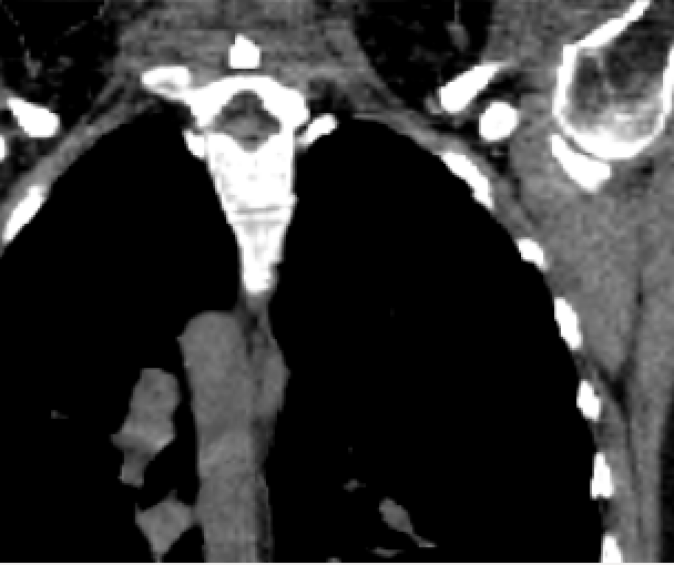

Figure 5: Upper thorax coronal views of the animated CT data of the patient pat3D𝑝𝑎𝑡3𝐷pat3D (a-d) deformed with the model of pat4D𝑝𝑎𝑡4𝐷pat4D. Rib artifacts are indicated by the yellow arrow in (c).

(a) First time point.

Refer to caption

(b) Second time point.

(c) Third time point.

(d) Fourth time point.